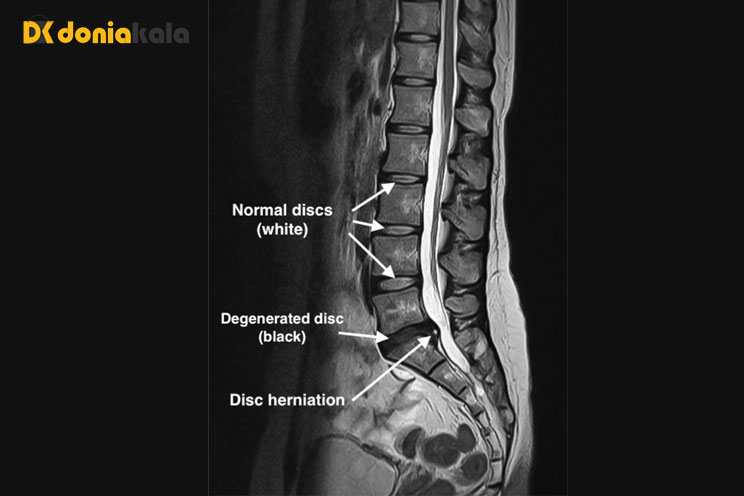

تصویربرداری رزونانس مغناطیسی ام آر آیی (MRI) : یک آزمایش تشخیصی که تصاویر سه بعدی از ساختارهای بدن را با استفاده از آهنرباهای قدرتمند و فناوری رایانه تولید می کند. می تواند طناب نخاعی، ریشه های عصبی و نواحی اطراف و همچنین بزرگ شدن، انحطاط و تومورها را نشان دهد.